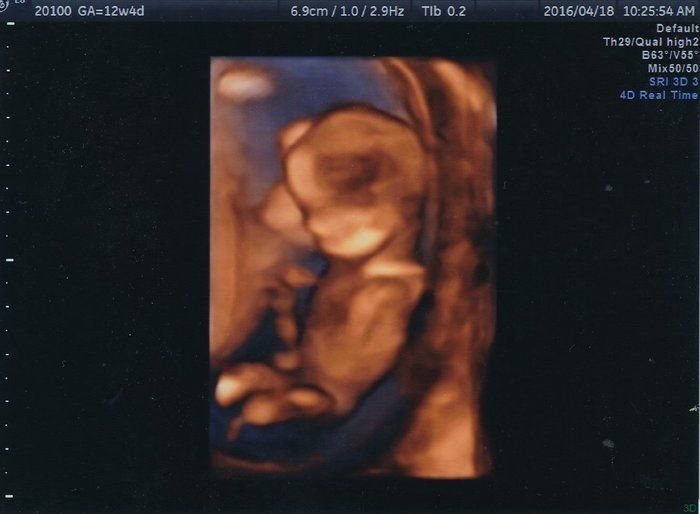

「背骨!足骨!ホントに人間がいる!」エコー画像を見る度、ゆっくり親になっていく私たち -